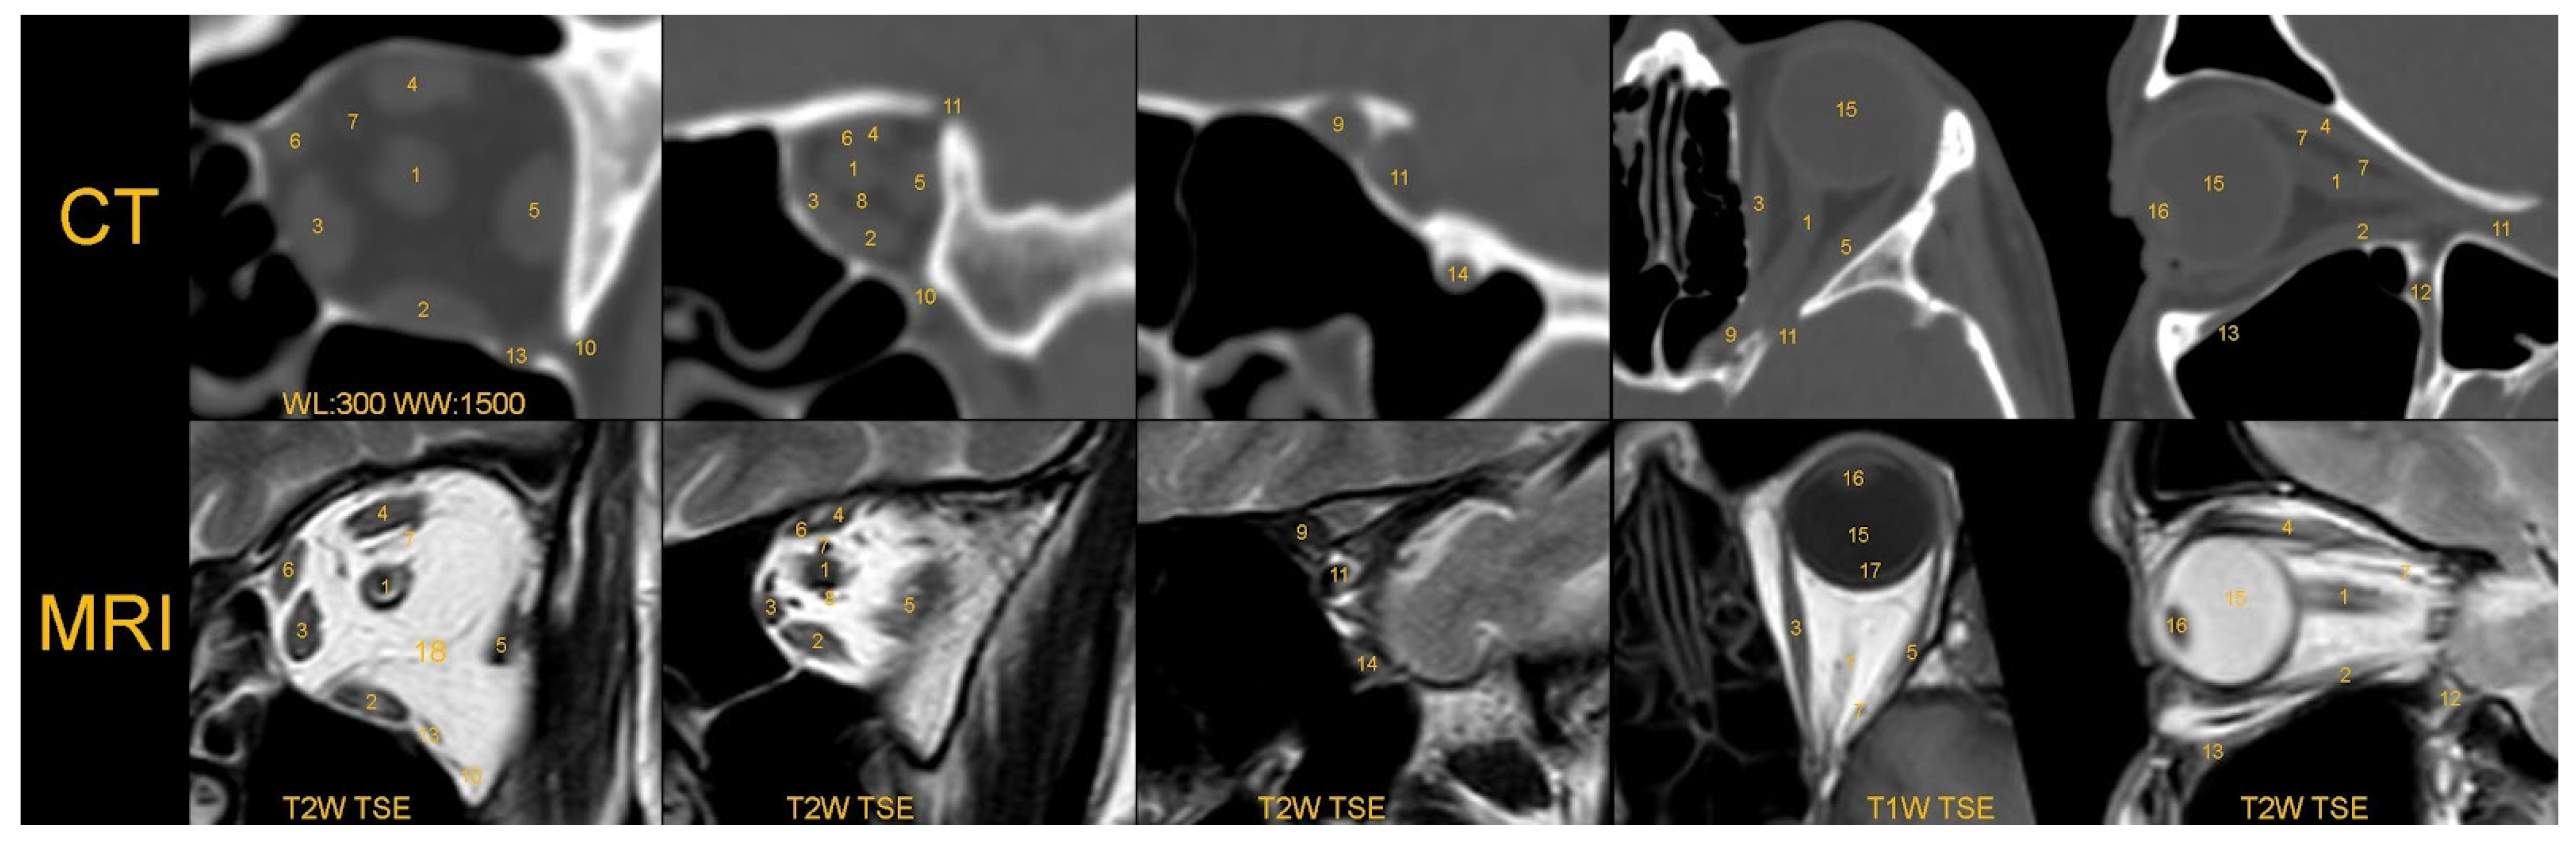

| CT | Computed tomography |

| MRI | Magnetic resonance imaging |

| WL | Window level |

| WW | Window width |